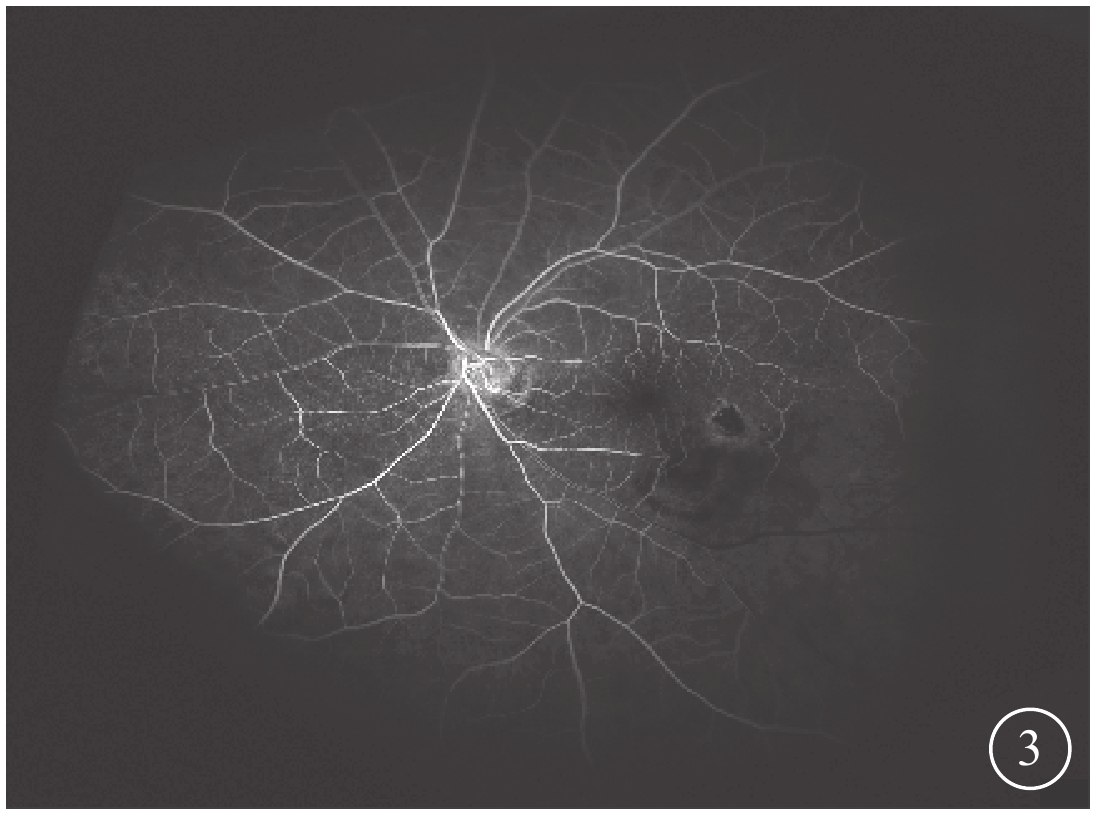

末次隨訪時,患眼BCVA為0.15~0.6,平均BCVA為0.42±0.24。患眼后房型人工晶狀體位正,黃斑部出血吸收。FFA檢查發現,患眼顳下視網膜動脈分支處強熒光點消失(圖3)。OCT檢查發現,患眼黃斑結構逐漸恢復(圖4)。所有患眼均未發生視網膜脫離、黃斑裂孔等并發癥。

圖3

圖1同眼手術后FFA像。顳下視網膜動脈分支處強熒光點消失

圖3

圖1同眼手術后FFA像。顳下視網膜動脈分支處強熒光點消失

末次隨訪時,患眼BCVA為0.15~0.6,平均BCVA為0.42±0.24。患眼后房型人工晶狀體位正,黃斑部出血吸收。FFA檢查發現,患眼顳下視網膜動脈分支處強熒光點消失(圖3)。OCT檢查發現,患眼黃斑結構逐漸恢復(圖4)。所有患眼均未發生視網膜脫離、黃斑裂孔等并發癥。

圖3

圖1同眼手術后FFA像。顳下視網膜動脈分支處強熒光點消失

圖3

圖1同眼手術后FFA像。顳下視網膜動脈分支處強熒光點消失